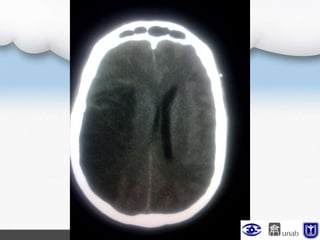

TAC de control

Se observa compromiso de 2/3 de la ACM derecha con

edema perilesional, compresión de

ventrículos laterales ipsilaterales se considera

debido a la edad del paciente, riesgo de edema

cerebral maligno, con criterios de

craniectomía temprana: edad, hemisferio no

dominante y edema, se sugiere valoración por neurocirugía

Escanografía cerebral simple con ligero edema

cerebral de predominio derecho con mínimo colapso

del ventrículo lateral ipsilateral.

Actualmente NO cumple criterios para procedimiento

quirúrgico